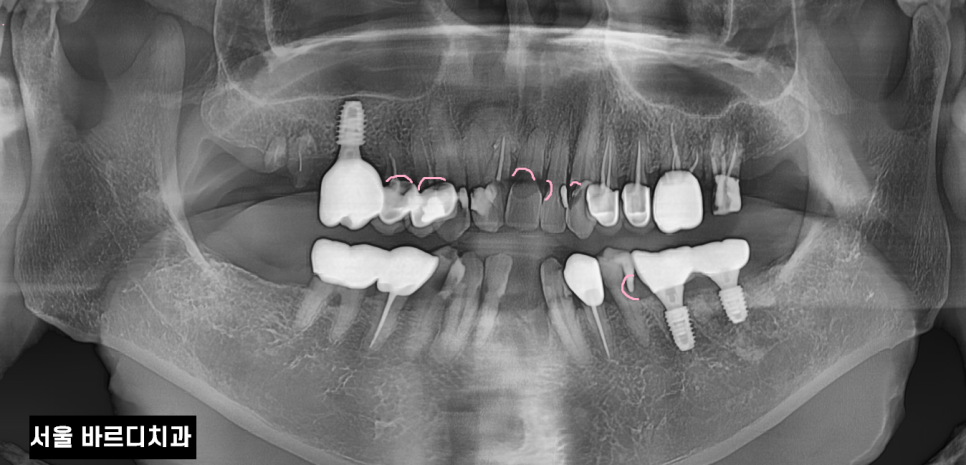

240521 신경관 좁아진 것좀 보세요~~

오늘 서울바르디치과를 내원하신 환자분은

입 마름으로 인하여 다발성 치근 우식증이 있었는데요.

뒤늦게 내원하셔서 증상이 심각하였고

(이미 부러진 치아도 있었어요ㅠㅠ)

신경치료 후 보철 치료로 진행할 수밖에 없었답니다.